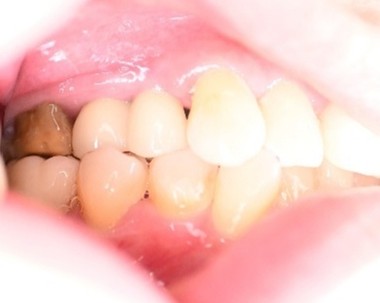

女性Kさん 70代(インプラント)

主訴

左下、ブリッジの支台になっていた奥のほうを抜歯したままになっている。ここのところを何とかしたい。

治療内容

ブリッジの奥に伸びていた部分を削り取り、インプラントを2本入れました。

所感

左下ブリッジのところを切り離し、奥を抜歯したままになっていました。このままでは、ブリッジの前方の支台になっていた歯に負担がかかり、将来抜歯になる可能性があることをお話ししました。歯がないところを補う方法には、部分入れ歯かインプラントがあることを説明すると、自分の歯と同じ感覚で食事ができるインプラントを選択されました。X-Guideを使用し埋入しました。口を大きく開けることができない方でしたので、X-Guideの長所のうちの一つを活かすことができました。

インプラント2本:¥363,000×2本=¥726,000(税込)

Before

青丸の部分を削り取りました

After